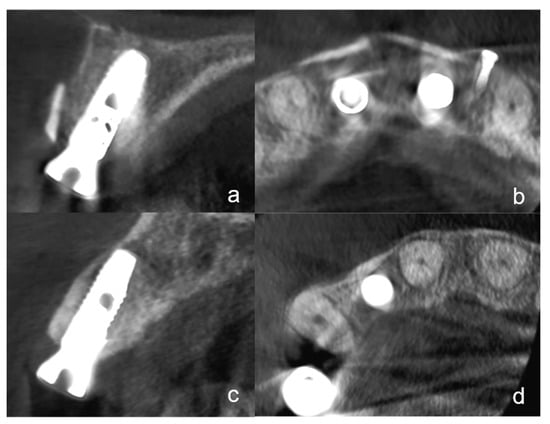

At the time of implant exposure (3 months after augmentation), a CBCT was made to assess the osseointegration, the buccal lamella, and the horizontal hard tissue loss. All implants were placed at the hard tissue level and the implant surfaces were completely covered by native bone or hard tissue graft (autogenous dentin or bone). To evaluate the horizontal bone loss the CBCTs at the time of implant exposure were analyzed. The hard tissue loss was assessed considering mesial and distal aspects. Only the highest value at the mesial or distal margin was included in the analyses. Additionally, the integrity of the buccal lamella was assessed using the CBCT (Figure 4a–d). Possible hard tissue loss with exposed buccal implant surfaces was noted.

3.2. Radiographic Evaluation

At the time of the follow-up, 3 months after augmentation with simultaneous implantation evaluation of the CBCTs showed two cases with horizontal hard tissue loss at the mesial or distal implant shoulder. One case with TST exhibited a hard tissue loss of 1 mm and one case with BST of 0.5 mm. There were no significant differences between the two groups at all three statistical levels. The integrity of the buccal lamella was preserved in all implants (Figure 4a,d). All implants were completely covered with hard tissue (no more than 1 mm loss).

In all cases with TST, the dentin shell was clearly visible. In some cases with BST, the bone shell was not visible in the CBCT or had a partial replacement resorption.

Figure 4. (a): A cone-beam computed tomography (CBCT) in the sagittal plane shows an implant regio 11 with the tooth-shell technique (TST) at the time of the implant exposure. The integrity of the buccal lamella is visible. The dentin shell does not appear to show any resorption. (b): The same CBCT in the axial plane with the implant in region 11 and another implant region 21. Two buccal dentin shells are clearly visible. (c): This figure shows a CBCT in the sagittal plane of an implant region 12 with BST at the time of implant exposure. At this plane, the complete integrity of the buccal lamella can be seen. The bone shell is no longer visible and appears to have undergone replacement resorption. (d): The same implant in the CBCT in the axial plane. No bone shell can be seen.